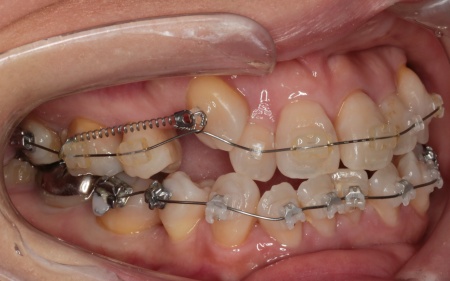

治療中

今回は審美性に配慮し、前歯には目立ちにくい透明のブラケットを、奥歯には耐久性のある金属製のブラケットを使用するハイブリッド矯正を選択しました。

ワイヤー矯正を進めていくなかで、右上の前歯2本(中切歯、側切歯)が骨の中で根がくっついている癒合歯(ゆごうし)であることが判明しました。

この影響で、側切歯の位置がずれたまま中切歯と一緒に動いてしまい、単独での正確な位置調整が難しい状態です。

そのため患者様と相談し、側切歯の表側に歯科用プラスチックを盛って見た目を整え、噛み合わせに支障が出ないよう慎重に調整を行う措置をとりました。

また歯を効率よく動かすため、顎の骨に矯正用の小さなネジであるインプラントアンカーを埋め込み、それを固定源とすることでしっかりと歯を動かしながら、歯列と噛み合わせのバランスを整えています。